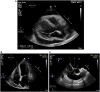

Figure 3

Echocardiography of the patient from March 2020.